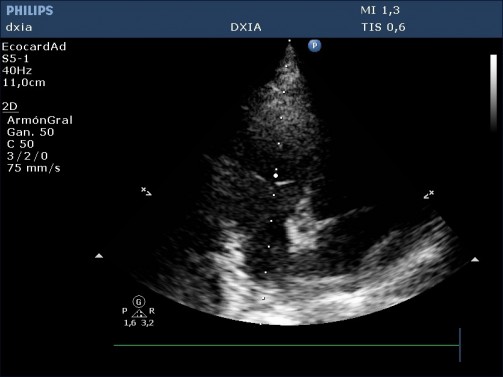

Conclusiones del estudio ecocardiográfico

Predominancia de cámaras derecha, con marcada dilatación de estas (AD y VD)

Leve engrosamiento de cúspides de la VT

Insuficiencia tricuspídea excéntrica de alta velocidad (4,2 m/seg)

Hipertrofia moderada de pared libre del VD y del SIV

No aplanamiento septal

Arteria pulmonar dilatada pero perfil flujo pulmonar debido a: